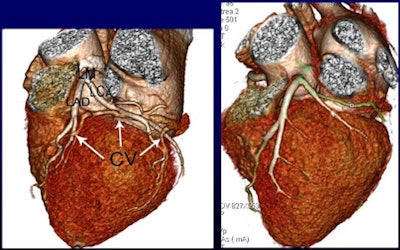

The researchers scanned more than 100 patients using contrast volumes of 0.8, 0.7, or 0.6 mL/kg, measuring CT attenuation in the ascending and descending aorta, left and right coronary arteries, and coronary sinus. CT values in the ascending and descending aorta and coronary arteries exceeded 300 HU in all three contrast groups.

The study team measured attenuation at regions of interest in the ascending and descending aorta, left and right coronary arteries, and coronary sinus.

CT values in the coronary sinus were 112.7, 93.7, and 81.2 HU for Groups A, B, and C, respectively (p < 0.001). CT values within the ascending and descending aorta and the coronary arteries were higher than 300 HU in all three contrast groups.